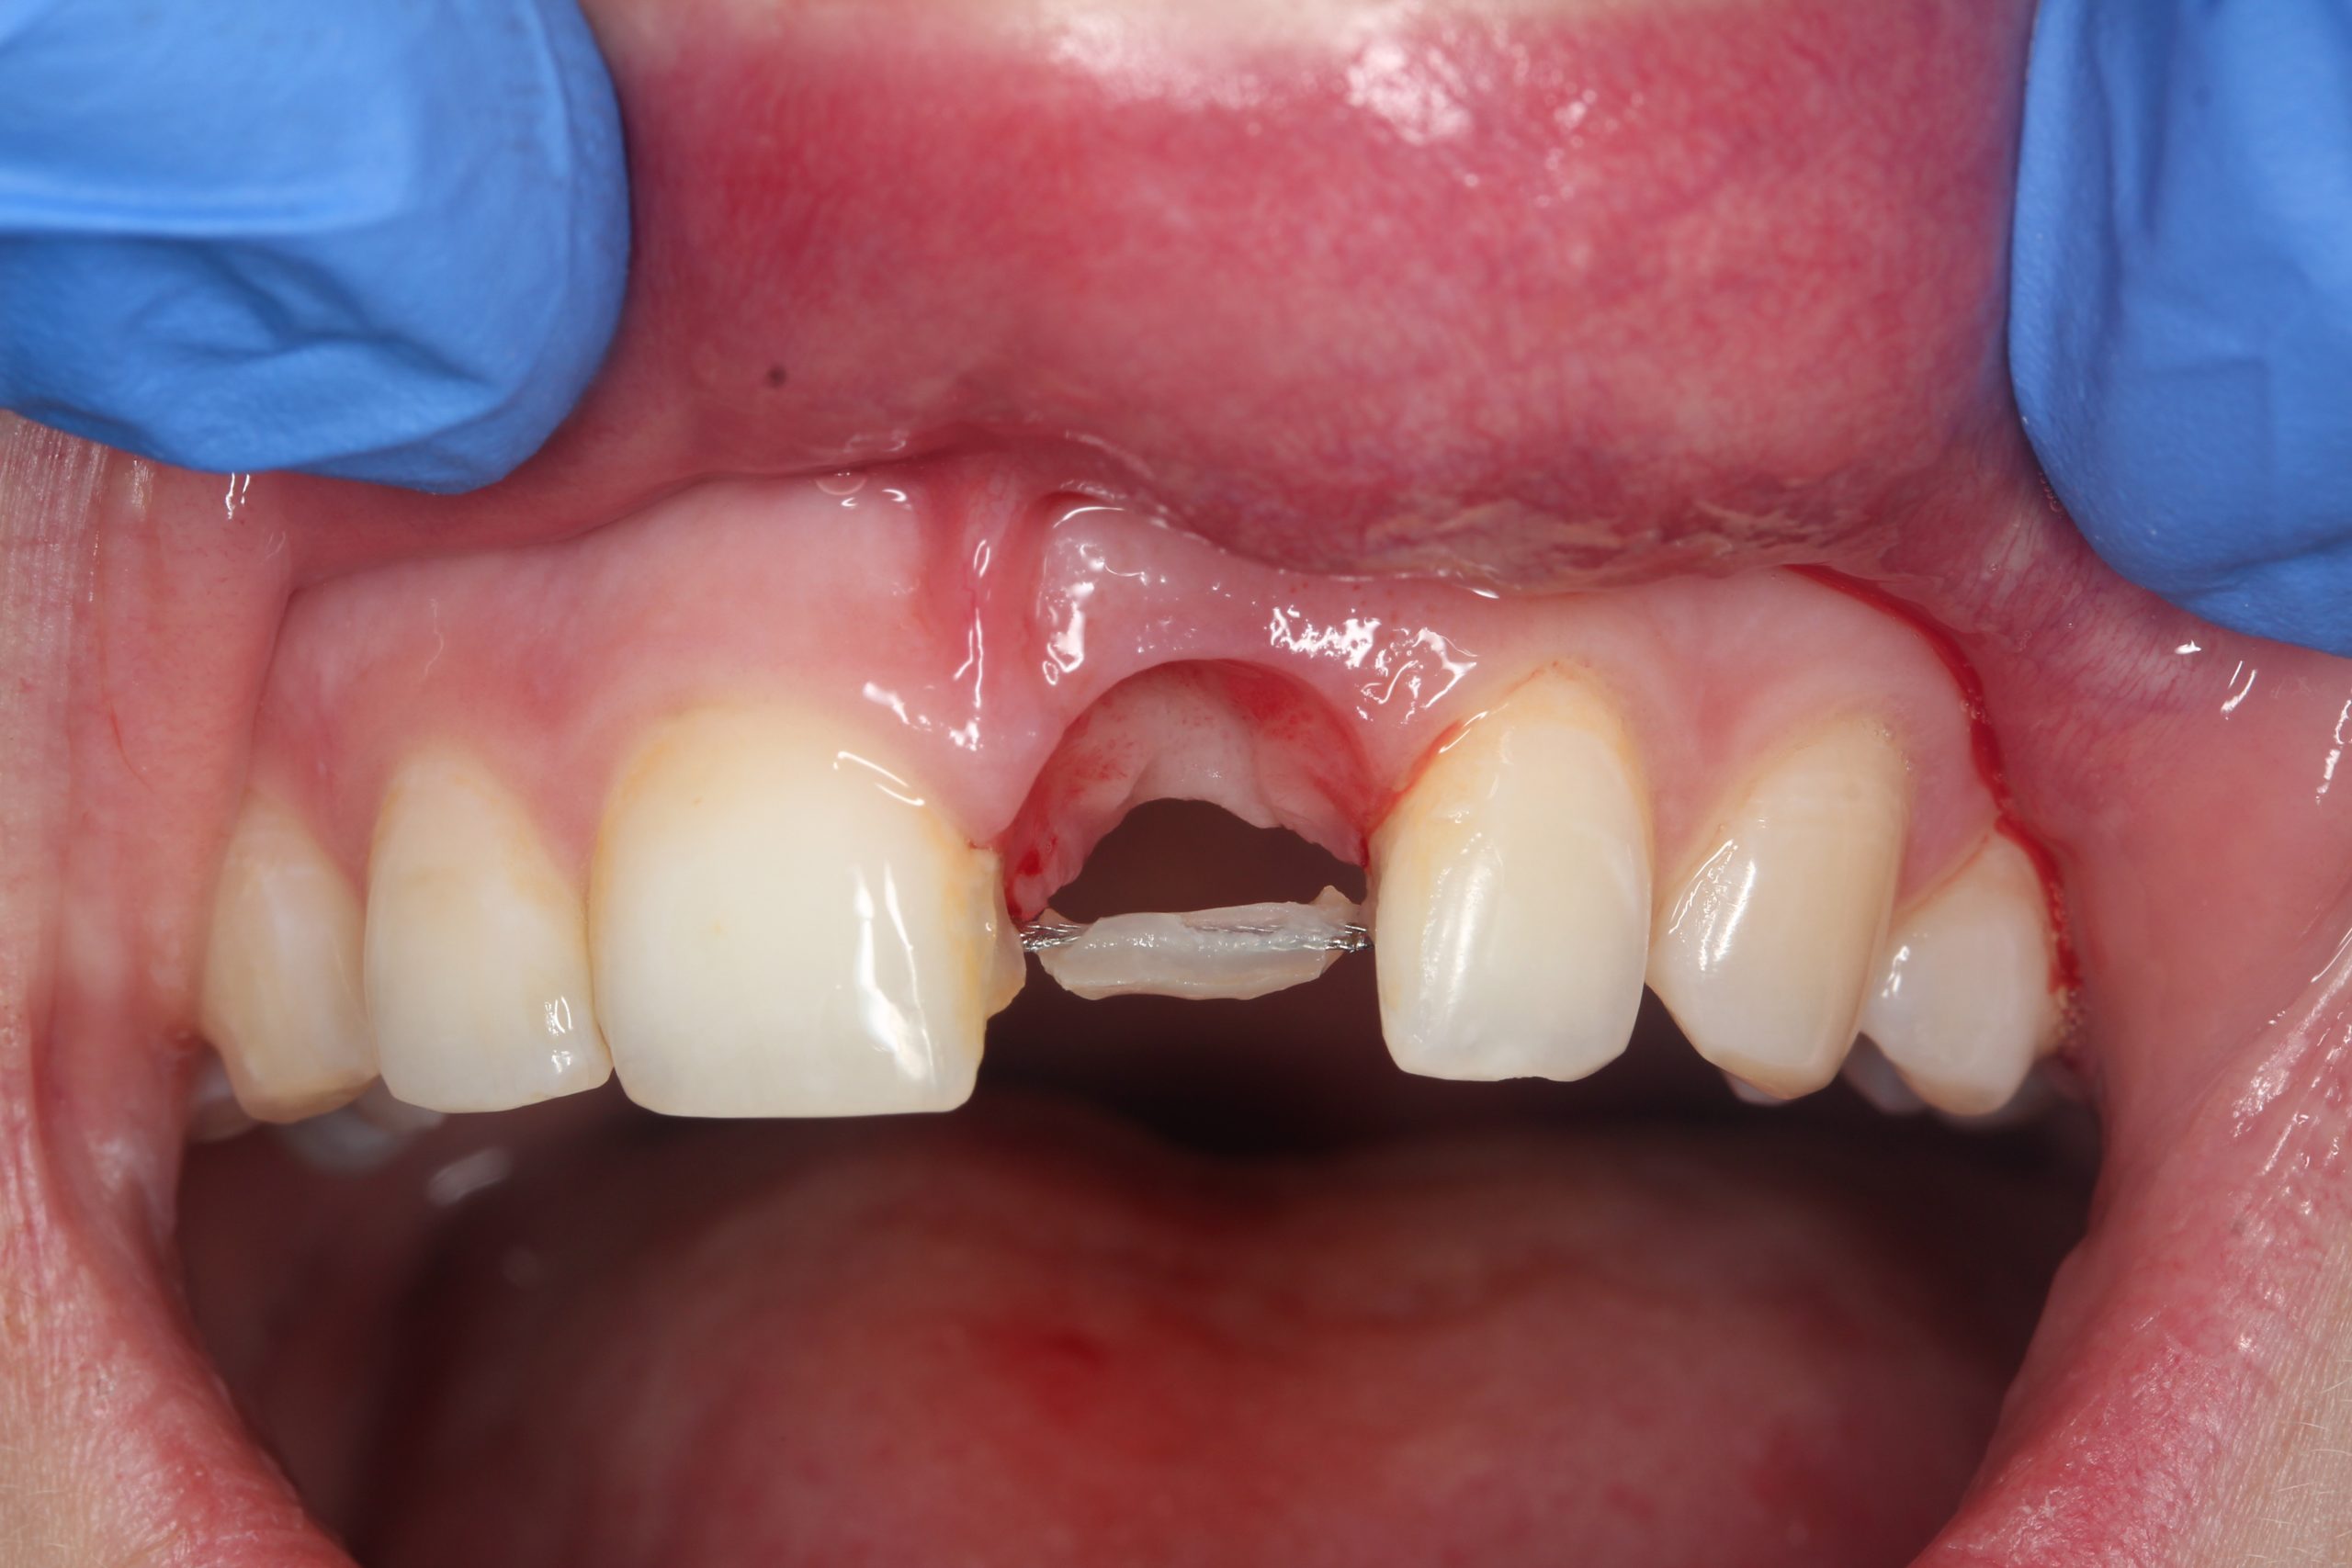

After extraction and excochleation, the extraction wound was revised. The vestibular wall of the socket was preserved except for the apical part. The tooth bed was only filled with an antibiotic-containing collagen cone.

The extracted tooth was used as a temporary restoration. The root was cut approximately 2 mm below the CEJ so that this part was embedded in the soft tissue. The crown was cemented to the adjacent teeth with composite.

After removal of the crown: a perfectly epithelialized extraction site and preserved interdental papillae. The wire splint with which the dental crown had been temporarily fixed was temporarily retained as a control element for inserting the implant.